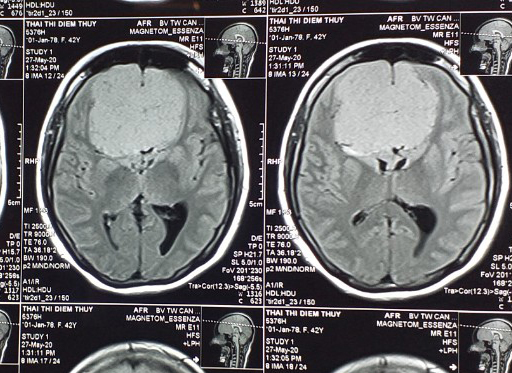

Bệnh nhân Thái Thị Diễm Thúy (SN 1978, ngụ TP Cần Thơ) bị đau đầu 3 tháng nay, bắt đầu từ trán lên đỉnh đầu, sau đó đau nửa đầu nhiều, đi mua thuốc uống không giảm, mắt bị mờ dần. Sau đó, chị Thúy được gia đình chuyển đến BVĐKTƯCT cấp cứu trong tình trạng đau đầu nhiều, thị lực hai mắt giảm, nhìn đôi, phù gai thị, mất mùi hoàn toàn…

| Hình ảnh u não siêu khủng trong đầu bệnh nhân Thúy. |

Kết quả chụp cộng hưởng từ có tiêm chất tương phản từ ghi nhận khối choáng chỗ ngoài vùng trán kích thước 6 x 6,5 x 5cm (bằng quả trứng), ép não thất hai bên, kết luận u màng não siêu khủng.